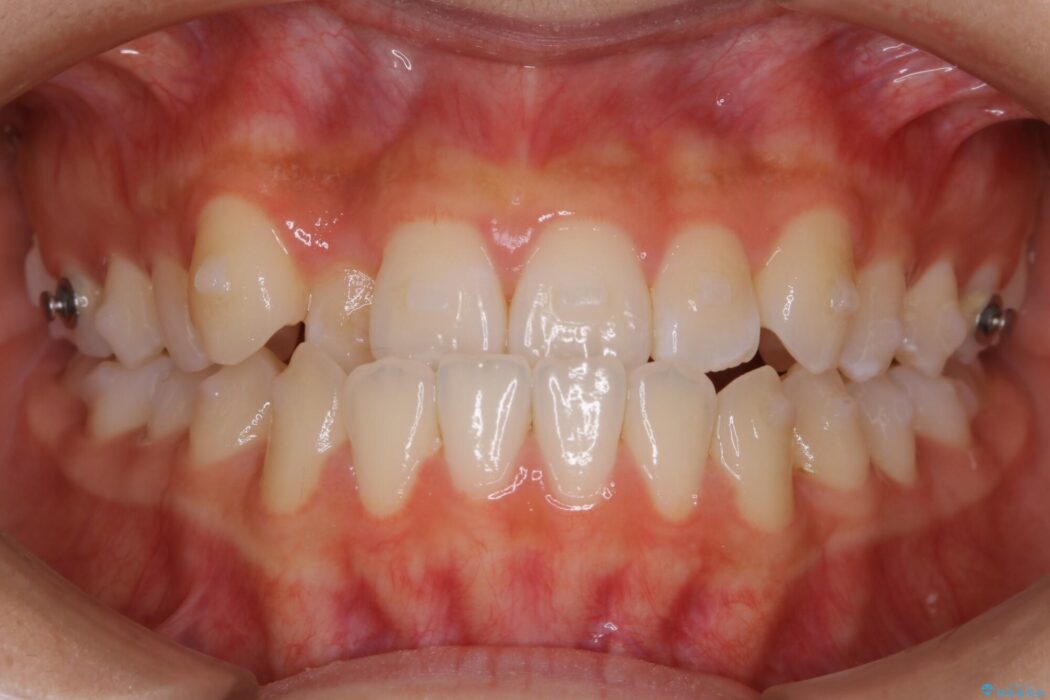

下の歯が上の歯より前に出ている受け口と前歯のガタガタ(叢生)について治療したいとのことで来院されました。

詳しく検査したところ、上顎の歯が舌側に倒れこんでしまっていることや歯列のガタガタなどにより口を閉じた時に上下の前歯の先端が接触してしまっていました。

更に深く噛もうと力を入れると、下顎が前方に突き出して前歯が当たらないように噛んでしまう機能性の反対咬合という診断となりました。